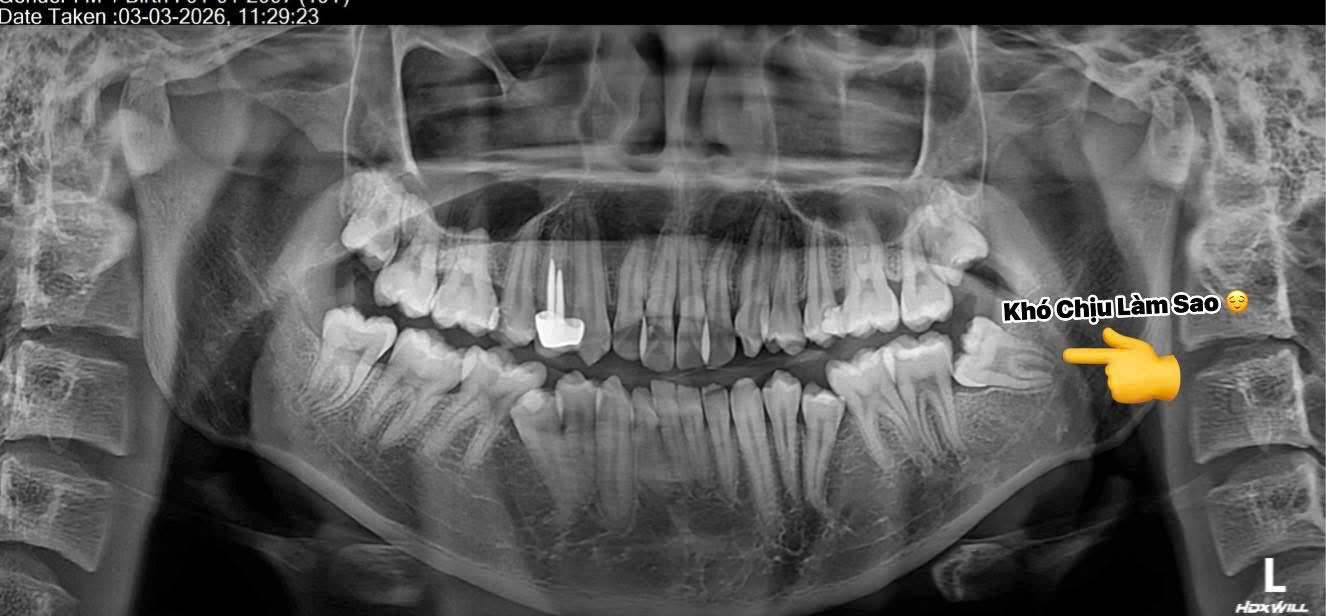

Bước 1: Thăm khám & chụp X-quang

Xác định hướng mọc của răng khôn mọc lệch